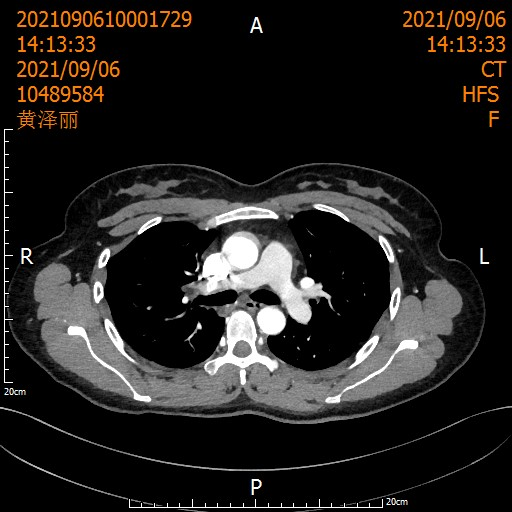

遵循《国际专家共识》,刘浩团队启动了术前2周期化疗联合3周期"卡瑞利珠单抗+紫杉醇/卡铂"治疗。

治疗后患者影像

当术后病理报告出炉时,所有人的激动难以言喻: 肺泡上皮增生,间质明显纤维化伴淋巴细胞浸润及淋巴滤泡形成,未见明显肿瘤细胞,切缘阴性,21枚淋巴结0转移——病理完全缓解(pCR)!

从T3到T0,从晚期到根治,这场医患携手创造的奇迹,让整个科室沸腾!